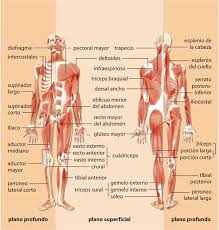

1181 × 1300 - gimolimpo.com

{"id":"Rohz-pKMmS4_0M:","isu":"gimolimpo.com","itg":0,"ity":"jpg","oh":1300,"ou":"http://www.gimolimpo.com/PAGINA%2062/musculosdorsales.jpg","ow":1181,"pt":"ANATOMIA

HUMANA","rid":"KhRkfq-OMAvQ7M","rmt":0,"rt":0,"ru":"http://www.gimolimpo.com/Paginas/ANATOMIA%20HUMANA.htm","s":"Visión

Frontal","sc":1,"th":236,"tu":"https://encrypted-tbn0.gstatic.com/images?q\u003dtbn:ANd9GcQbfHPY9kAjUYom1KfJZWZndoE6JCieaUeZv2ENDRKwDT_ucpXeRQ","tw":214}